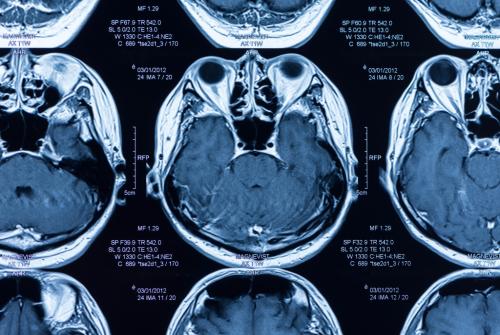

MR (Manyetik Rezonans Görüntüleme)